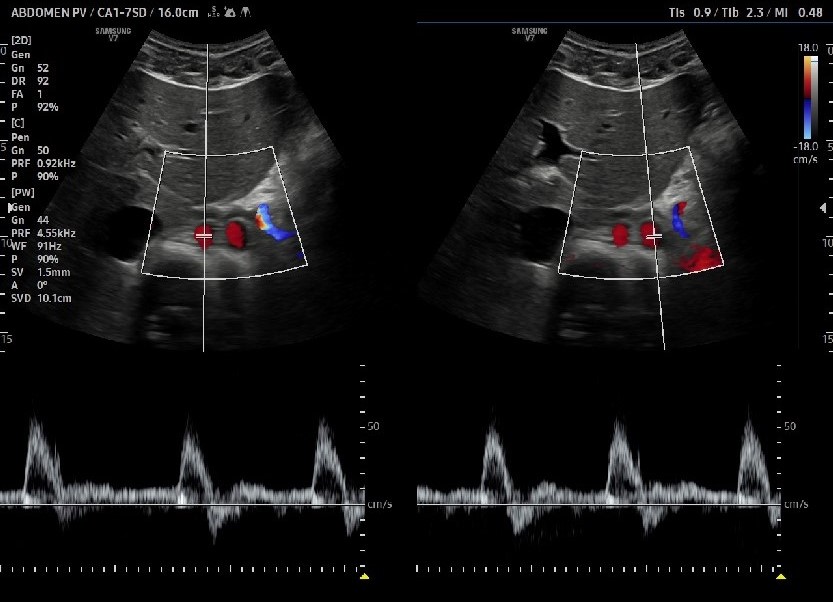

Fig. 3. Presents spectral Doppler recordings from a triplex ultrasound examination, illustrating flow patterns within both the right and left lumina of a double aorta artifact.

Spectral Doppler (pulsed wave Doppler) waveforms remain physiologically normal in the presence of the artifact. They can be used to distinguish between actual pathology and artifact, as accurate duplications or dissections will show abnormal flow patterns.